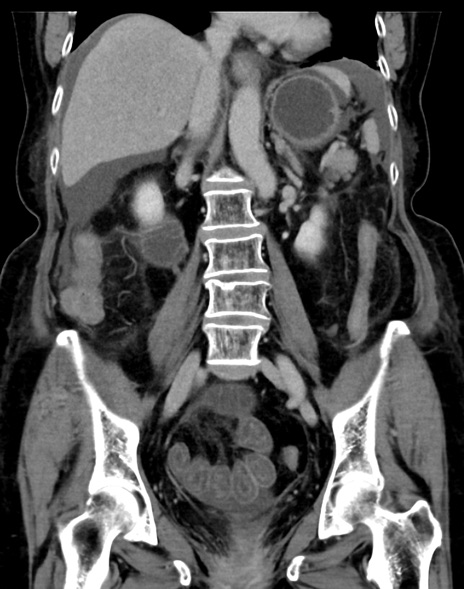

症例13 CT(冠状断像)1日半後